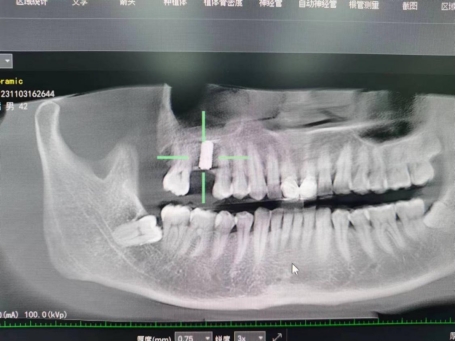

武先生术前检查图

据了解,53岁的武先生,因右上后牙缺失多年,缺失的牙齿给他造成了不小的烦恼,影响到了正常咀嚼功能。在了解到91直播 口腔科能开展种植牙手术以后,武先生前来咨询,经过仔细全面的口腔检查和CT检查、检验等检查,武先生符合种植牙条件,决定实施右上后牙区种植牙的修复方案。本次手术由陈河林博士主刀,黄魁副主任做助手,在口腔中心成功完成该院首例种植牙手术,手术历时约30分钟,术中微创操作,患者全程无痛,术后无不良反应,整个诊疗过程舒适、安全、精准,经术后CT检查种植体位置精确。